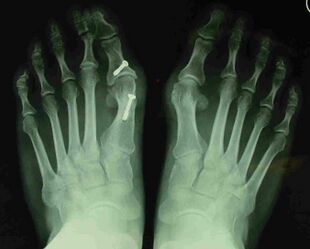

Late deformity recurrence can happen after osteotomy (bone-breaking) procedures because osteotomy surgeries do not specifically stabilize first metatarsal bone.

For recurrence correction after fusion procedure (Fig. 9) Metatarsus primus varus deformity and pain recurred 6 months after modified Lapidus procedure and it could also be again corrected by the syndesmosis procedure.